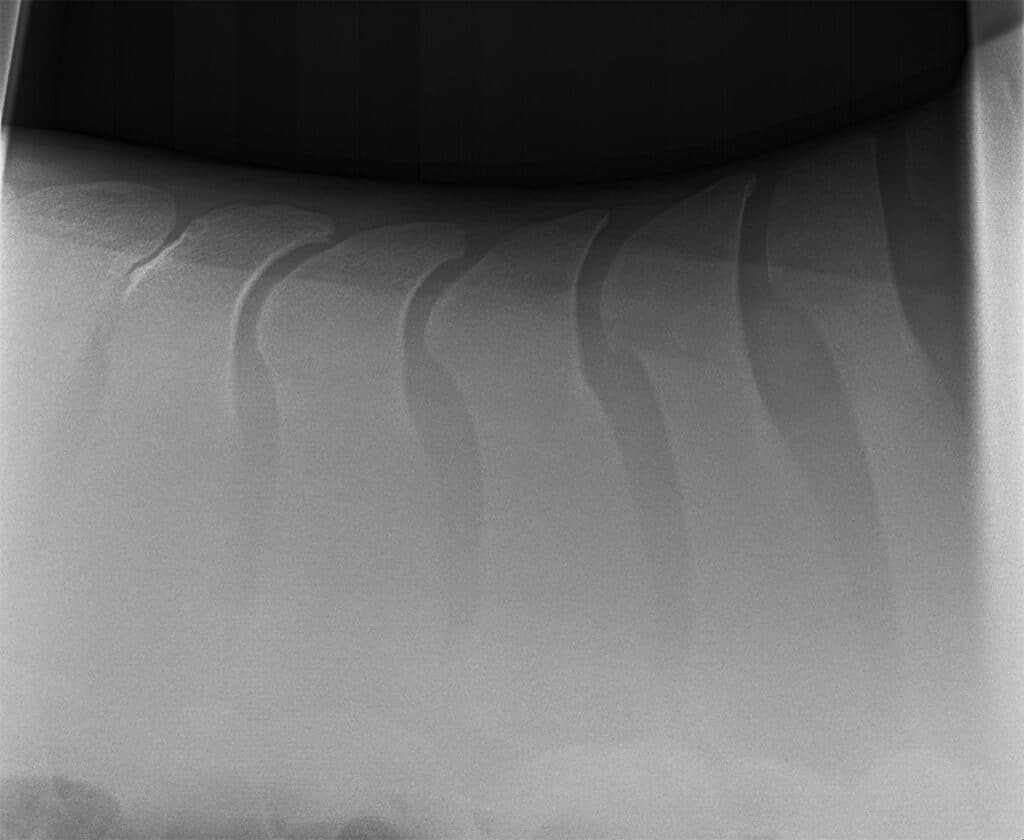

An X-ray showing both normal spacing of the spines, as well as kissing spines (left hand side) where the close dorsal spinous processes in between show some inflammation and degeneration occurring.